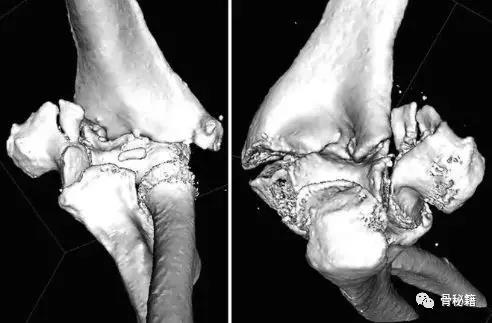

详细的术前评估

X线、CT、神经、等等